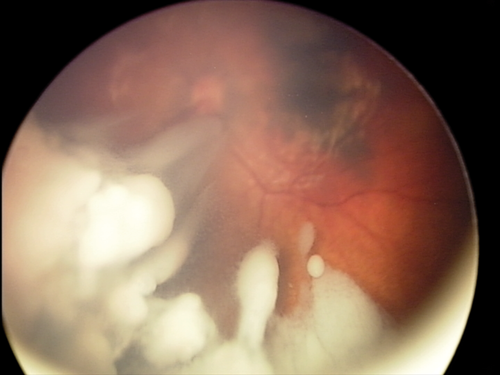

- Direct injection of drugs into the vitreous cavity intravitreal chemotherapy (IVC).

The long held principle of avoiding entering the eye was challenged with the introduction of this new treatment in 2009, and has been a paradigm shift in management. Vitreous disease is less responsive to all other forms of treatment, and has been a major cause of failure in the past. IVC involves pars-plana injection of one or two chemotherapeutic agents (typically melphalan, topotecan, or carboplatin) directly into the vitreous, after anterior chamber paracentesis, with cryotherapy to the injection site. This highly effective treatment is inexpensive, and does not require a specialised set-up. It can therefore be offered in most retinoblastoma centres in developing countries, which has reduced enucleation rates markedly in recent years (Figure 2).

Figure 2. Successful treatment of extensive vitreous disease with intravitreal chemotherapy.